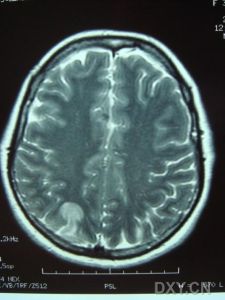

3.MRI是本病的重要診斷工具側腦室周圍及半卵圓中心可見均勻分布的點狀和結節狀T2WI高信號,基底核和腦橋也可見多數病人腦血管造影無異常,曾報告1例患者小動脈嚴重狹窄,另2例患者腦血管造影后神經體徵加重PET檢查僅1例嚴重基底核損傷的躁狂病人提示皮質代謝降低皮膚活檢是腦外部檢查的新手段,皮膚活檢發現嗜鋨顆粒樣物(GOM)沉積有重要診斷價值。可伴明顯抑鬱躁狂和自殺傾向,注意繼發的肺部感染尿路感染及褥瘡等。

影像學上有類似Binswanger病的表現,MRI顯示在腦室周圍白質、腦幹、小腦中腳、基底節區和丘腦部位多發性小的線狀、點狀病灶,可在皮質下對稱融合成片狀。CADASIL臨床確診標準:在可能CADASIL診斷標準的同時,與第19號常染色體連鎖和(或)病理證實有顆粒狀嗜鋨性物質沉積改變的小動脈病。可能為CADASIL的診斷標準:①50歲前發病;②出現下列臨床表現中至少2條:症狀持久的腦卒中發作、偏頭痛、明顯的情感異常、皮質下痴呆;③無腦血管病的危險因素;④常染色體顯性遺傳證據;⑤MRI顯示腦白質異常,而無腦皮質梗死灶。

⑥影像學檢查:MRI顯示非典型性腦白質病。可見,腦室周圍多發的梗死灶及白質變性,可累及兩側半球皮層、白質及腦室周圍、基底節、橋腦白質等部位。

影像學檢查示:患者姐弟的CT均可見,但當地的CT顯示欠清楚。患者的頭顱CT可見多發白質變性;MRI清晰可見多發白質變性及小梗死病灶,病灶大小不一,均呈長T1、長T2信號,病灶累及雙側半球、腦室周圍、腦幹、橋腦,小腦未見病灶;梗死灶分布在底節區,MRA(血管的磁共振影像)顯示顱內血管正常。